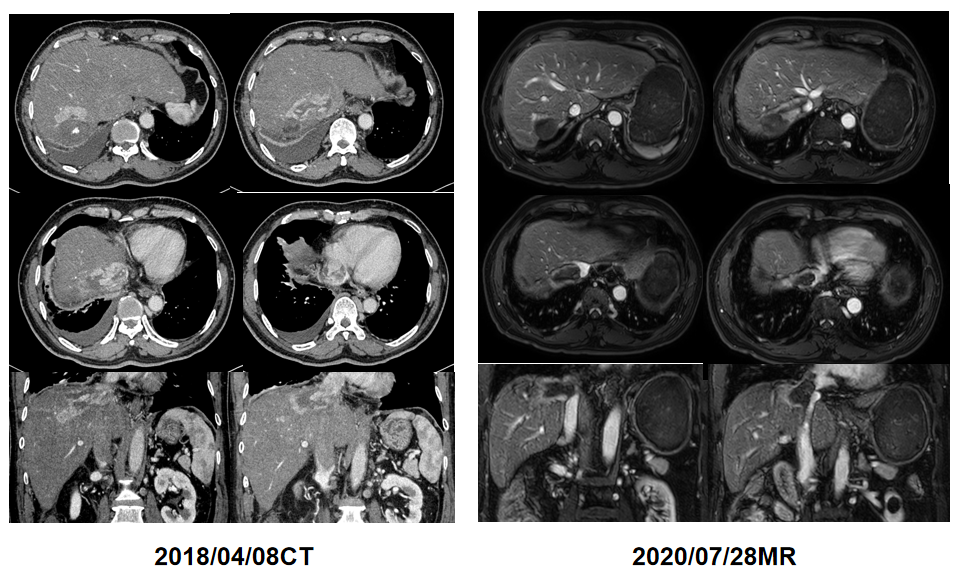

病例简介患者女性,46,因体检发现肝占位1周,于2019年2月就诊于浙江大学医学院附属第二医院。7年前因左乳腺肿物于外院行左乳腺癌改良根治术,术后未行放化疗。&n...